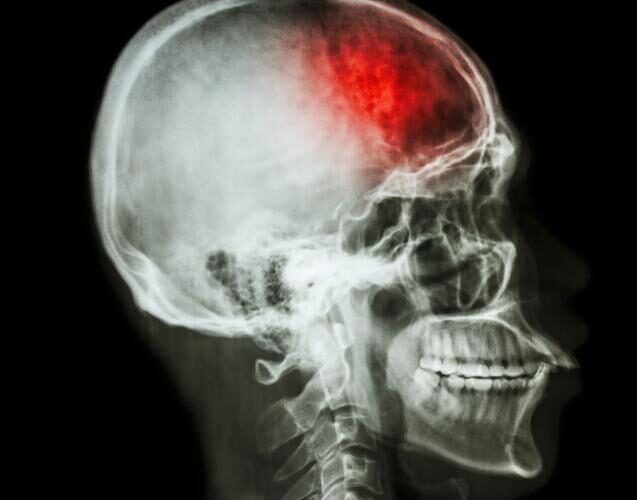

failure to treat a stroke with tPA

A tissue plasminogen activator (tPA) is a form of thrombolytic therapy used to treat strokes. This medication can break down blood clots to promote blood flow, allowing the brain to receive oxygen in the event of an acute ischemic stroke.

A stroke is a cerebrovascular accident that inhibits blood flow to the brain, depriving it of oxygen. The longer that the brain goes without oxygen, the more damaged it becomes. Strokes are not just damaging, but they are also incredibly deadly. According to the American Stroke Association, 1 in 21 deaths in the U.S. were the result of a stroke in the year 2020.

People can suffer from a stroke as a result of either a ruptured blood vessel within the brain or a blood clot in the brain. Ischemic strokes are caused by clots, whereas hemorrhagic strokes are caused by broken blood vessels. Both can cause the brain to suffer from oxygen deprivation, but since these two kinds of strokes are caused by different things, they have to be treated differently.